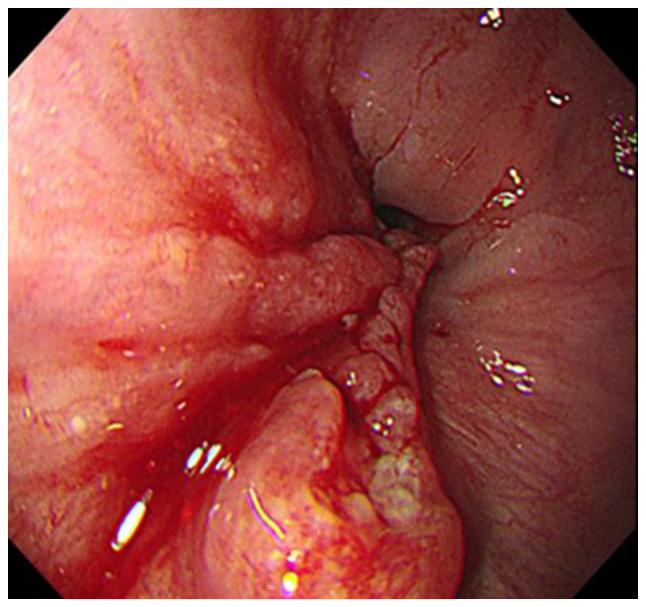

胰腺转移的频率有限,而食道鳞状细胞癌转移的频率则更加有限。有报道称,一些患者的这类转移性病灶可进行根治性切除,但这些手术能给患者带来的生存益处尚未明确确定。本研究中的患者是一名 54 岁的男性,被诊断为下胸段食管癌。计算机断层扫描显示,胰腺尾部有一个 2 厘米的肿瘤。由于没有发现其他明显的远端转移灶,患者同时接受了外科手术,切除了食管鳞状细胞癌和胰腺转移灶。组织病理学检查证实,两份标本均为鳞状细胞癌。自切除术后,患者已痊愈 9 个月。对迄今为止所有相关病例的文献回顾也表明,所有出现胰腺转移的食管癌患者的原发肿瘤部位都是下胸段食管。完全同时切除食管鳞状细胞癌和胰腺单发转移瘤是有益的,可能会产生良好的疗效。然而,由于相应的报告数量较少,还需要进一步的研究来证实手术的益处。

The frequency of metastasis to the pancreas is limited, and the frequency of metastasis of a squamous cell carcinoma of the esophagus is limited even further. The curative resection of this type of metastatic lesion has been reported for some patients; however, the survival benefit that can be attributed to these procedures has not yet been clearly determined. The patient examined in the present study was a 54-year-old man who was diagnosed with a lower thoracic esophageal cancer. Computed tomography revealed a 2-cm tumor at the tail of the pancreas. Since no other obvious distal metastases were observed, the patient underwent simultaneous surgical procedures, excising the esophageal squamous cell carcinoma and the pancreatic metastasis. A histopathological examination confirmed squamous cell carcinoma in both specimens. The patient has been free of disease for 9 months since the resection. A literature review of all relevant cases to date also demonstrated that the primary tumor site in all cases of patients with esophageal cancer presenting with metastasis to the pancreas was the lower thoracic esophagus. Complete simultaneous resections of esophageal squamous cell carcinoma and a solitary metastasis to the pancreas is beneficial and may produce favorable outcomes. However, due to the reduced number of corresponding reports, further studies are required for the confirmation of the benefits of surgery.